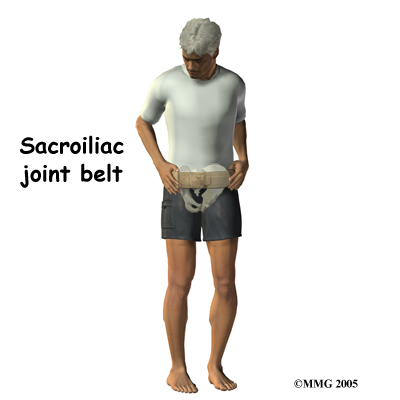

Unfortunately, few muscles actually connect to both the sacrum and the pelvis and therefore although you strengthen the weak muscles, stabilizing the SI joint completely can be more difficult in comparison to stabilizing other joints. Your SI joint may continue to move relatively more than normal and cause you ongoing discomfort with certain activities or when your muscles get tired. To combat this overall increased motion and to aid in alignment your therapist may suggest that you use a SI belt to help stabilize the joint. An SI belt is worn over the SI joints and around the hip area to help compress the joint together in order to create increased stability. Wearing an SI belt can often ease pain during activity and allow you to exercise comfortably. Many pregnant women find these belts particularly helpful. Using tape on the SI joint area, hips, and low back can also help to ease some of your pain, so your therapist may try doing this either before suggesting a belt, or in conjunction with doing so.